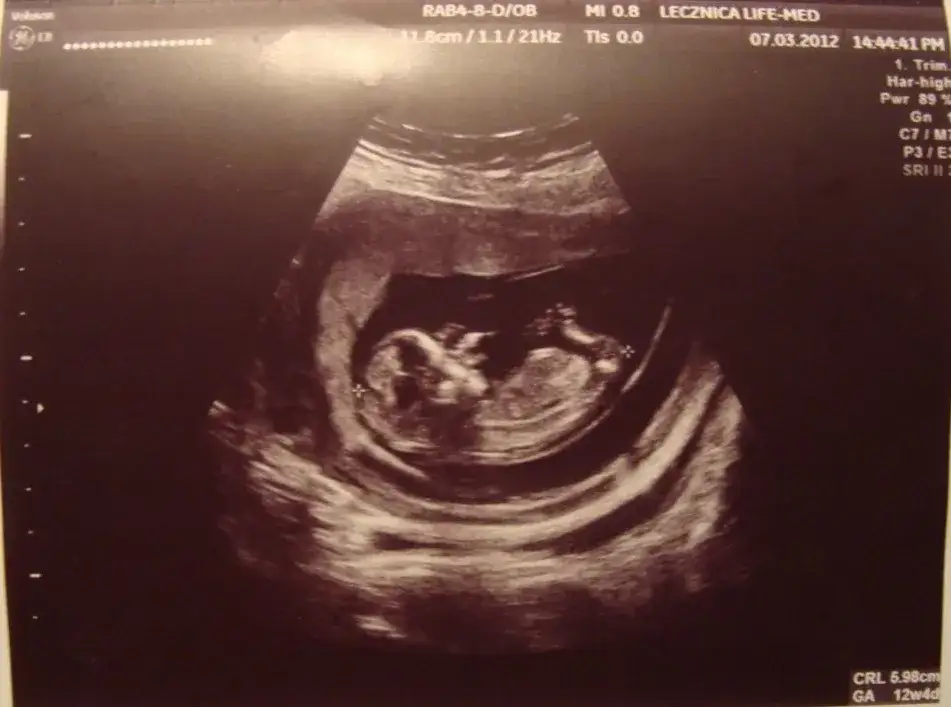

Jakie informacje można uzyskać z badań ultrasonograficznych?

Badania ultrasonograficzne w 13 tygodniu ciąży dostarczają cennych informacji o zdrowiu płodu i jego rozwoju. Ultrasonografia pozwala na ocenę wielkości płodu, co jest istotne dla określenia, czy rozwija się on zgodnie z oczekiwaniami. Można również zobaczyć, jak rozwijają się jego narządy wewnętrzne oraz zewnętrzne cechy, takie jak kształt głowy czy długość kończyn. Ponadto, badanie to umożliwia wykrycie ewentualnych nieprawidłowości, co jest kluczowe dla wczesnej interwencji w przypadku wykrycia problemów.

Ultrasonografia jest również ważna dla potwierdzenia daty porodu, co pozwala na lepsze planowanie opieki prenatalnej. Dzięki tym badaniom rodzice mogą zobaczyć swojego maluszka i zyskać pierwsze wyobrażenie o tym, jak wygląda ich dziecko. To doświadczenie może być emocjonujące i pełne radości, a także dostarcza informacji, które są nieocenione dla zdrowia matki i dziecka.